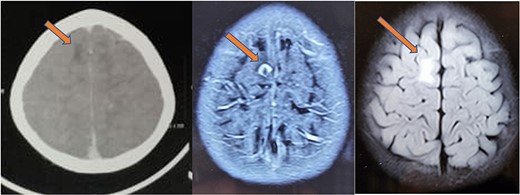

At 1-month follow-up, the patient had complete resolution of pain and swelling. Local USG back showed no evidence of any remnant lesion. At the 6-month follow-up, an MRI of the brain was done that showed a major reduction in the size of the lesion and resolution of perilesional edema (Fig. 7). At 1-year follow-up, the patient was found to be completely symptom-free, managing his activities of daily life, very well.

Repeat MRI at 6 months showing resolved changes with reduction in size of the lesion with resolution of perilesional edema.